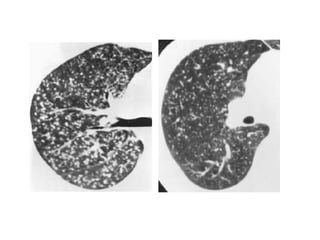

49-year-old woman with persistent and progressive cough, dyspnea, and hypoxemia,

prompting biopsy of her lungs, which revealed chronic desquamative interstitial

pneumonia (DIP) related to extensive cigarette smoking history, CT images through

mid and lower lungs show patchy ground-glass opacities in all lobes of both lungs

with peripheral predilection accompanied by lower lobe bronchial wall thickening, note

small cysts scattered mostly in right lung in regions of ground-glass attenuation,

finding that can occur in DIP